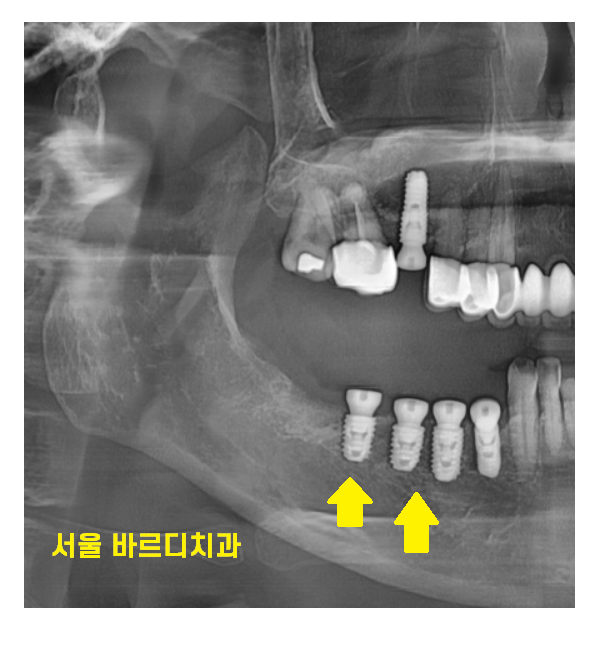

x-ray를 찍어보면

치아가 기울어진게 보이는데 말이죠

빠진 어금니 방치하다가

치아가 쓰러져

해당 환자분은 임플란트를 심을 공간이

부족하셨습니다.